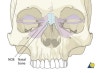

2) Naso-Orbital-Ethmoidal(NOE) fracture

(1) Fracture disrupting : Medial orbit + Nose +  Ethmoid sinus   (2) Medial canthal tendon slings globe to medial  orbital wall   (3) In NOE fracture, the tendon pulls fragment  laterally causing telecanthus